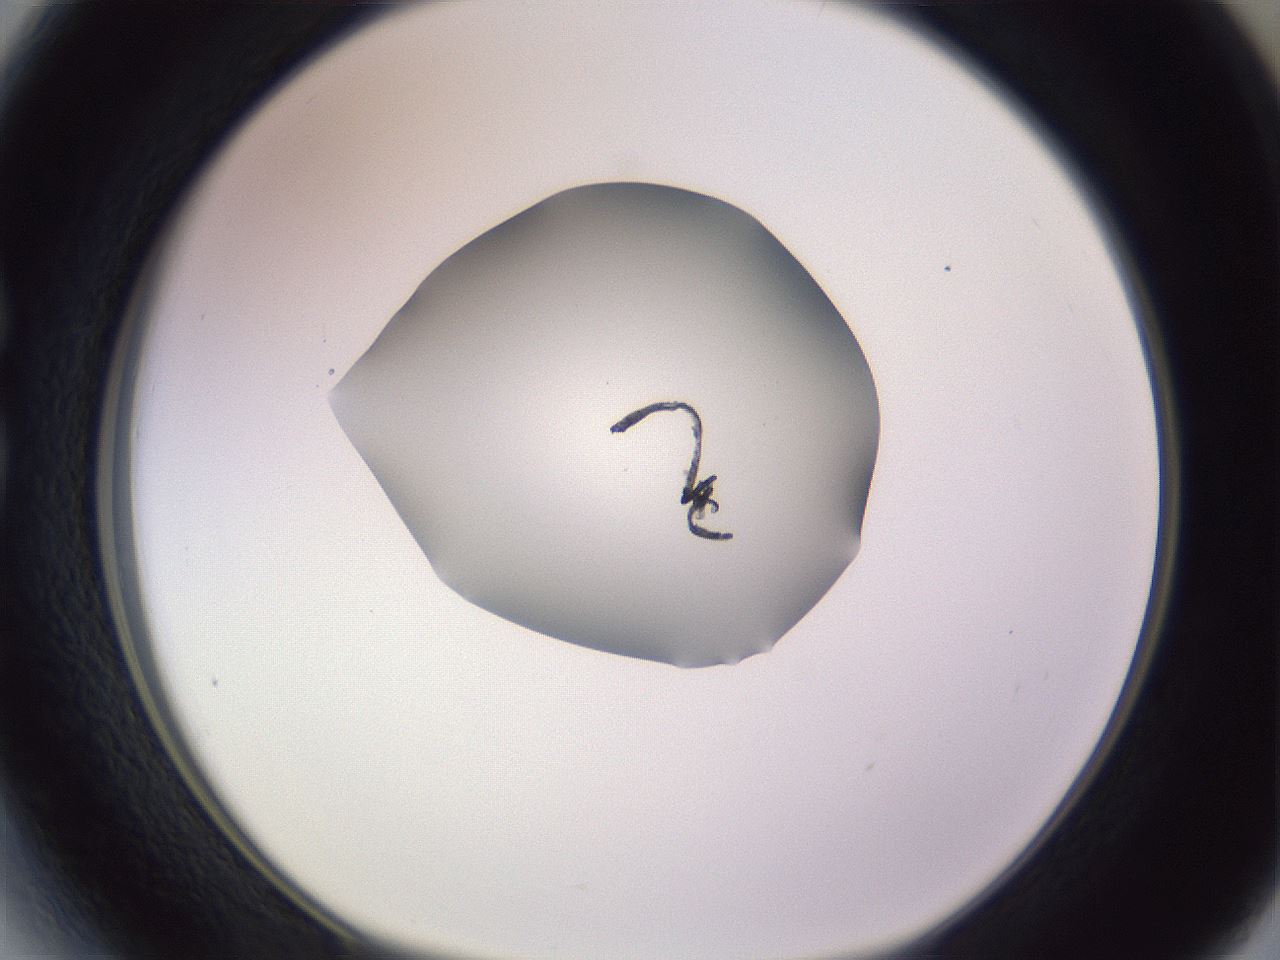

folderID605_plateID1605_batchID6721_wellNum27_profileID1_d1_r104680_ef.jpg